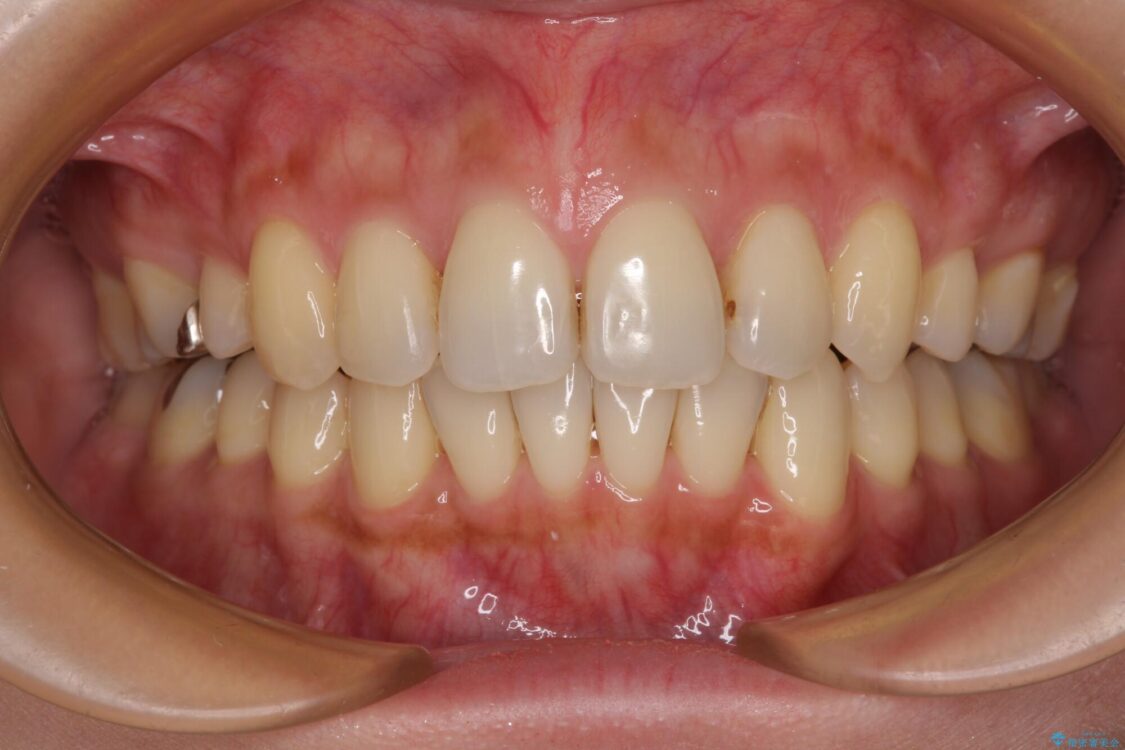

治療後について

インビザラインにて抜歯矯正を行うと、高頻度で奥歯が咬み合わなくなります。

また、抜歯スペースに向けて奥歯が移動する際、必ず傾斜して移動するため、仕上がりの咬み合わせはワイヤー矯正と比べて明らかに劣ります。

抜歯スペースが閉じてからも咬みにくさ改善のためマウスピース矯正を継続するため、治療期間は長期化します。

治療後

• 上顎前歯の突出を軽減 インビザラインによる抜歯矯正 治療後画像